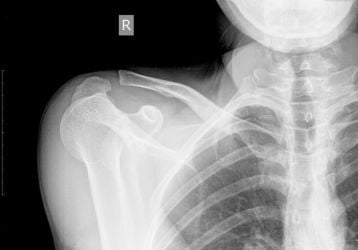

Вывих ключицы — симптомы травмы и методы лечения

Как отличить вывих ключицы от перелома, что предпринять сразу после травмы, как правильно фиксировать руку для заживления.